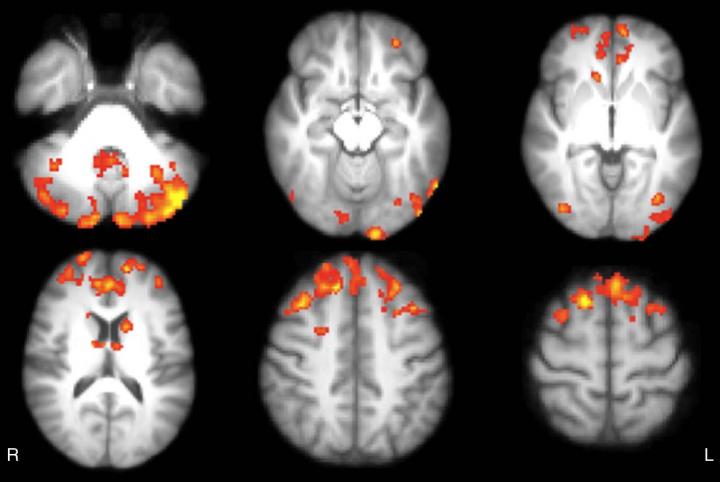

Axial statistical maps show areas of reduced thalamic functional connectivity in patients with MS compared with that in healthy subjects. Patients exhibited significantly lower FC in clusters located in the cerebellum, frontal and occipital cortices, caudate nucleus, and thalamus, bilaterally.